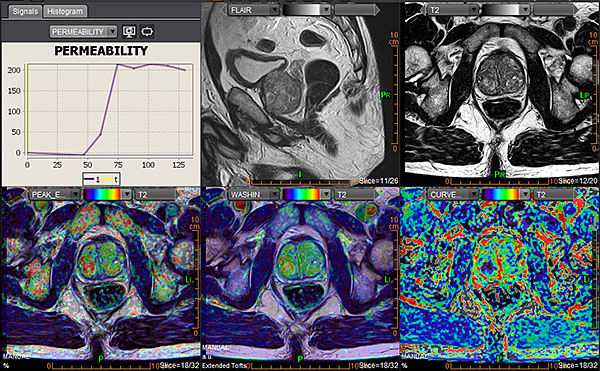

Додаток Prostate Streamlined.

Спеціальні програми Olea SphereTM для аналізу передміхурової залози включають в себе розширені можливості для оцінки дифузії та якісної оцінки перфузії. Також пропонують ефективний мультипараметричний аналіз усіх доступних послідовностей для візуалізації простати. В додатках реалізовано аналіз кінетики та кількісних даних на основі надійних математичних моделей. Програми передміхурової залози включають звіт PI-RADS® 2 для покращення виявлення, характеристики та вірогідності встановлення діагнозу раку простати. Цей програмний пакет стандартизує виклад протоколів опису, а також вказує рівень підозри або ризик виникнення клінічно значущих пухлин.